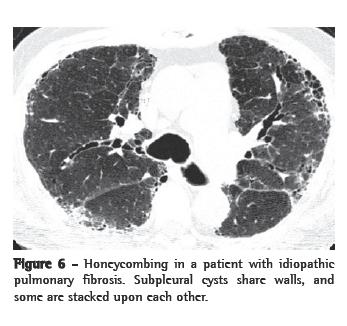

Honeycombing

Honeycomb lung remodeling (honeycombing) reflects the end stage of a number of diseases that cause parenchymal destruction. It presents a characteristic HRCT pattern, with subpleural, thick-walled cysts that share walls and, when advanced, are often stacked in multiple layers (Figure 6). It is typically accompanied by other signs of fibrosis (traction bronchiectasis and reticulation). Honeycombing is highly suggestive of a pathologic diagnosis of usual interstitial pneumonia (UIP), although it can be attributable to other diseases (Chart 3). Honeycombing seen on HRCT scans is often considered diagnostic of UIP in patients presenting the appropriate clinical profile, and the majority of such patients will not be subjected to surgical lung biopsy. Because bilateral honeycombing on HRCT scans is considered diagnostic under these conditions, it is vitally important for the radiologist to be confident that honeycombing is truly present before describing it.